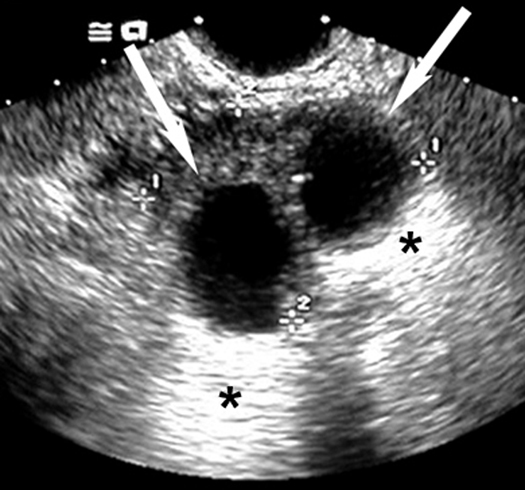

Simple Anechoic Renal Cysts

Arrows points to cyst.

* Points to  good through transmission of echoes behind the cyst.